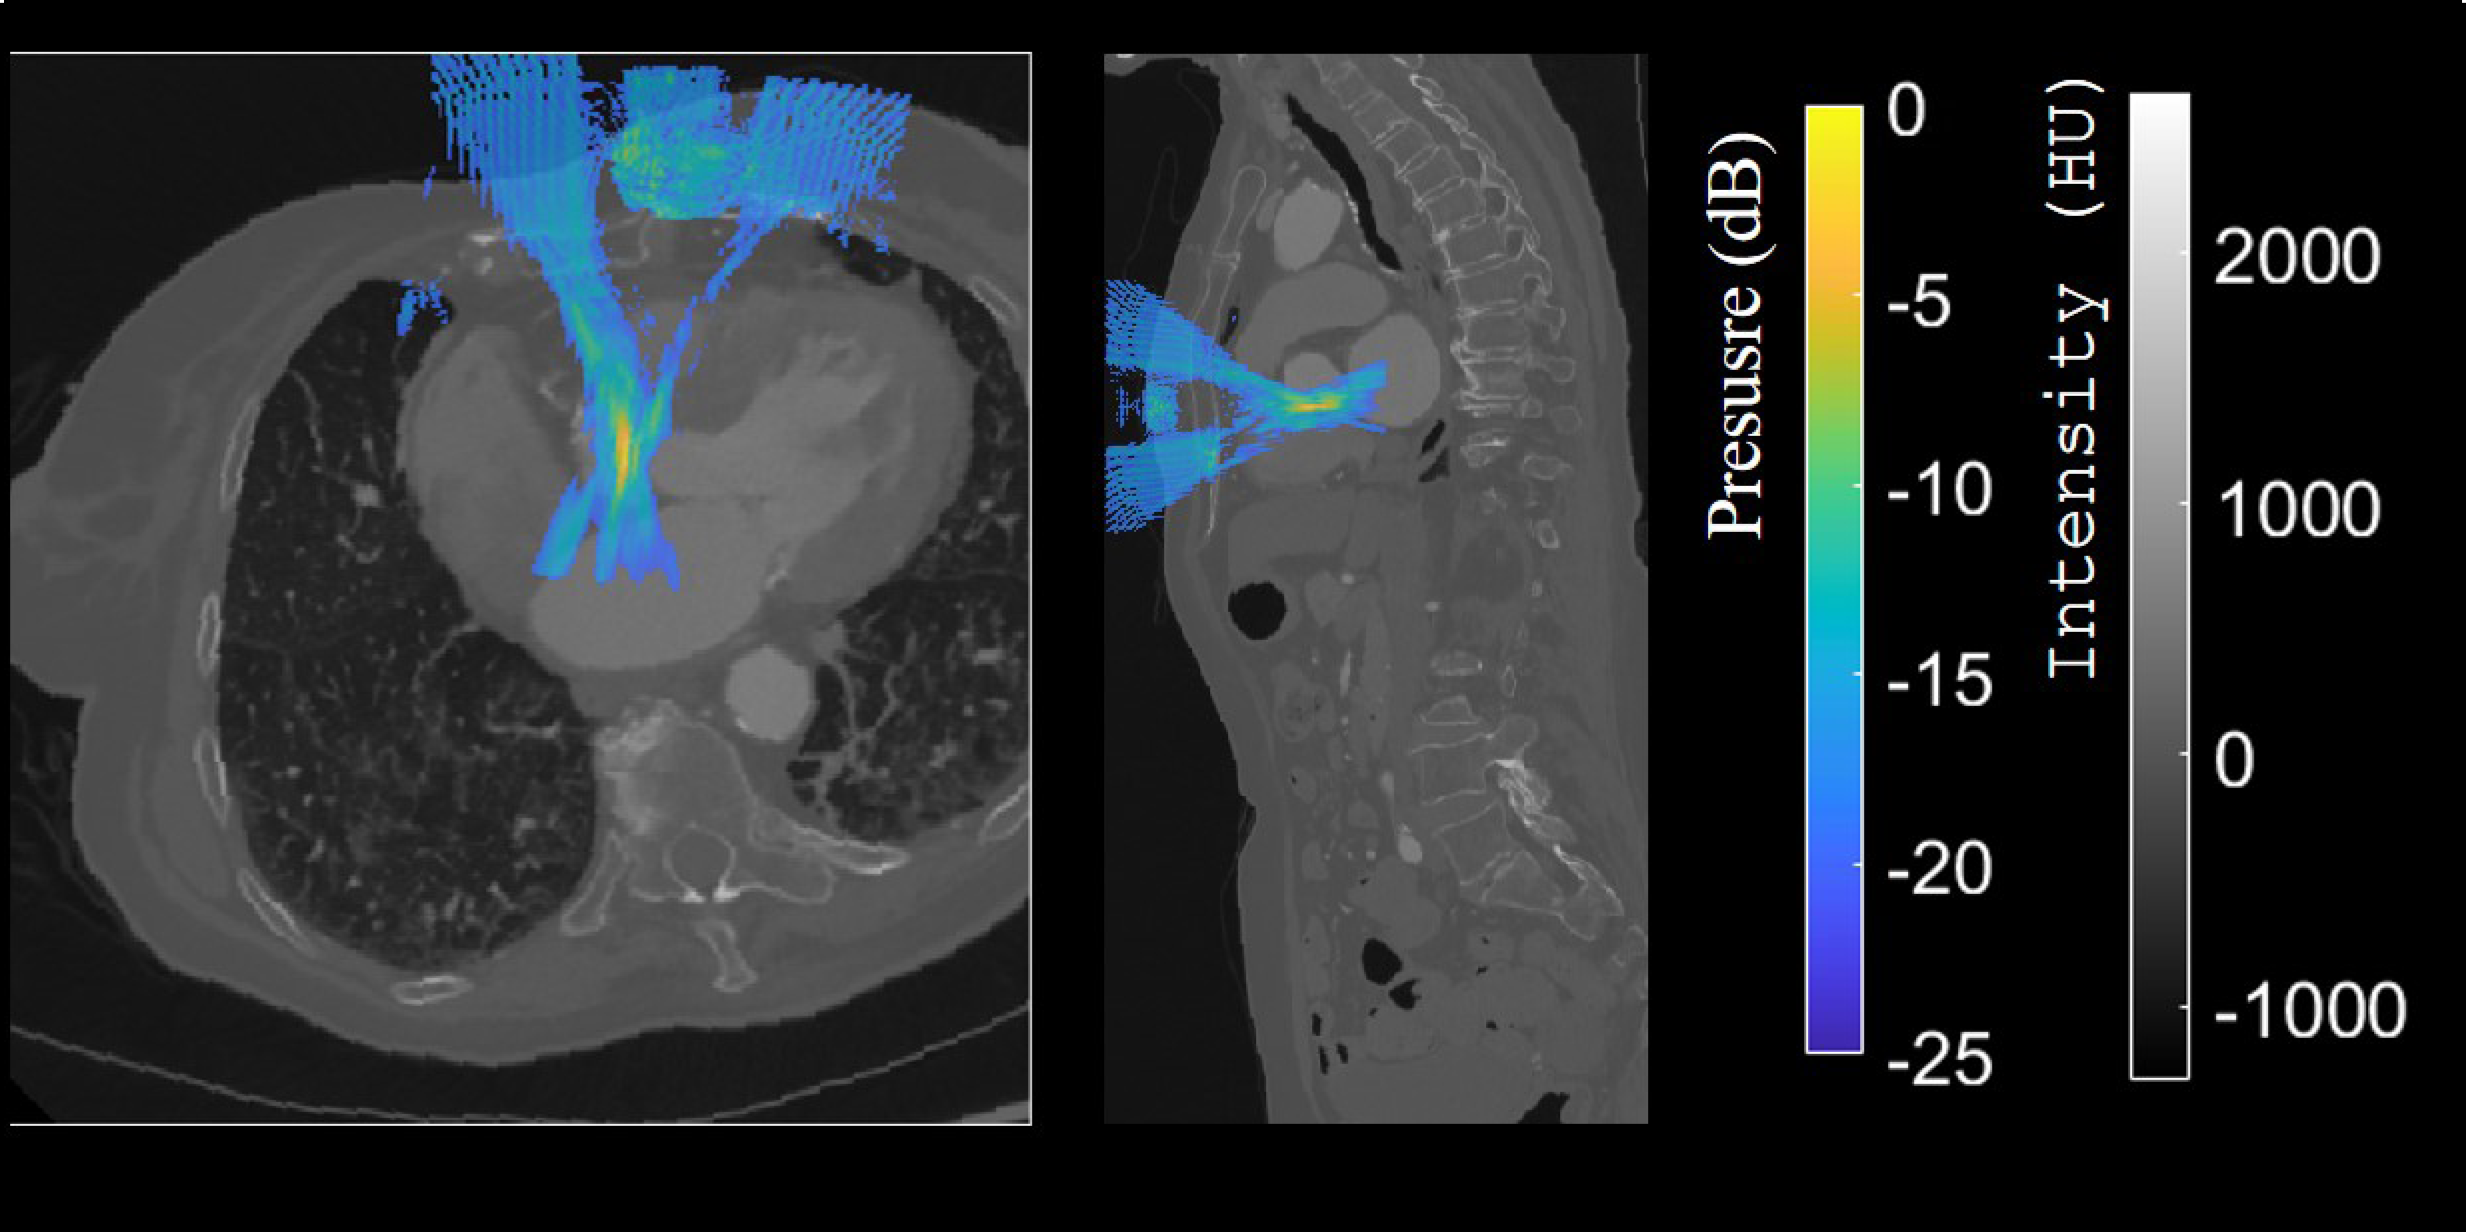

For the first time, whole-organ blood flow dynamics can be mapped at micrometric resolution using an ultrasound multi-lens probe — demonstrated in vivo in the heart, kidney, and liver.

The innovation relies on a multi-lens ultrasound probe (8 × 10 cm, 252 elements), each element equipped with a tiny acoustic lens. This design, inspired by optics, enables an unprecedented combination of wide coverage and high resolution — two features that had been mutually exclusive until now.

The probe achieves:

- imaging volumes up to 120 × 100 × 82 mm³,

- a spatial resolution around 100 µm,

- and ultrafast acquisition at 312 volumes per second.

These performances allow the visualisation of both large vessels and the finest microcirculation, revealing the complex vascular networks that sustain tissue function.